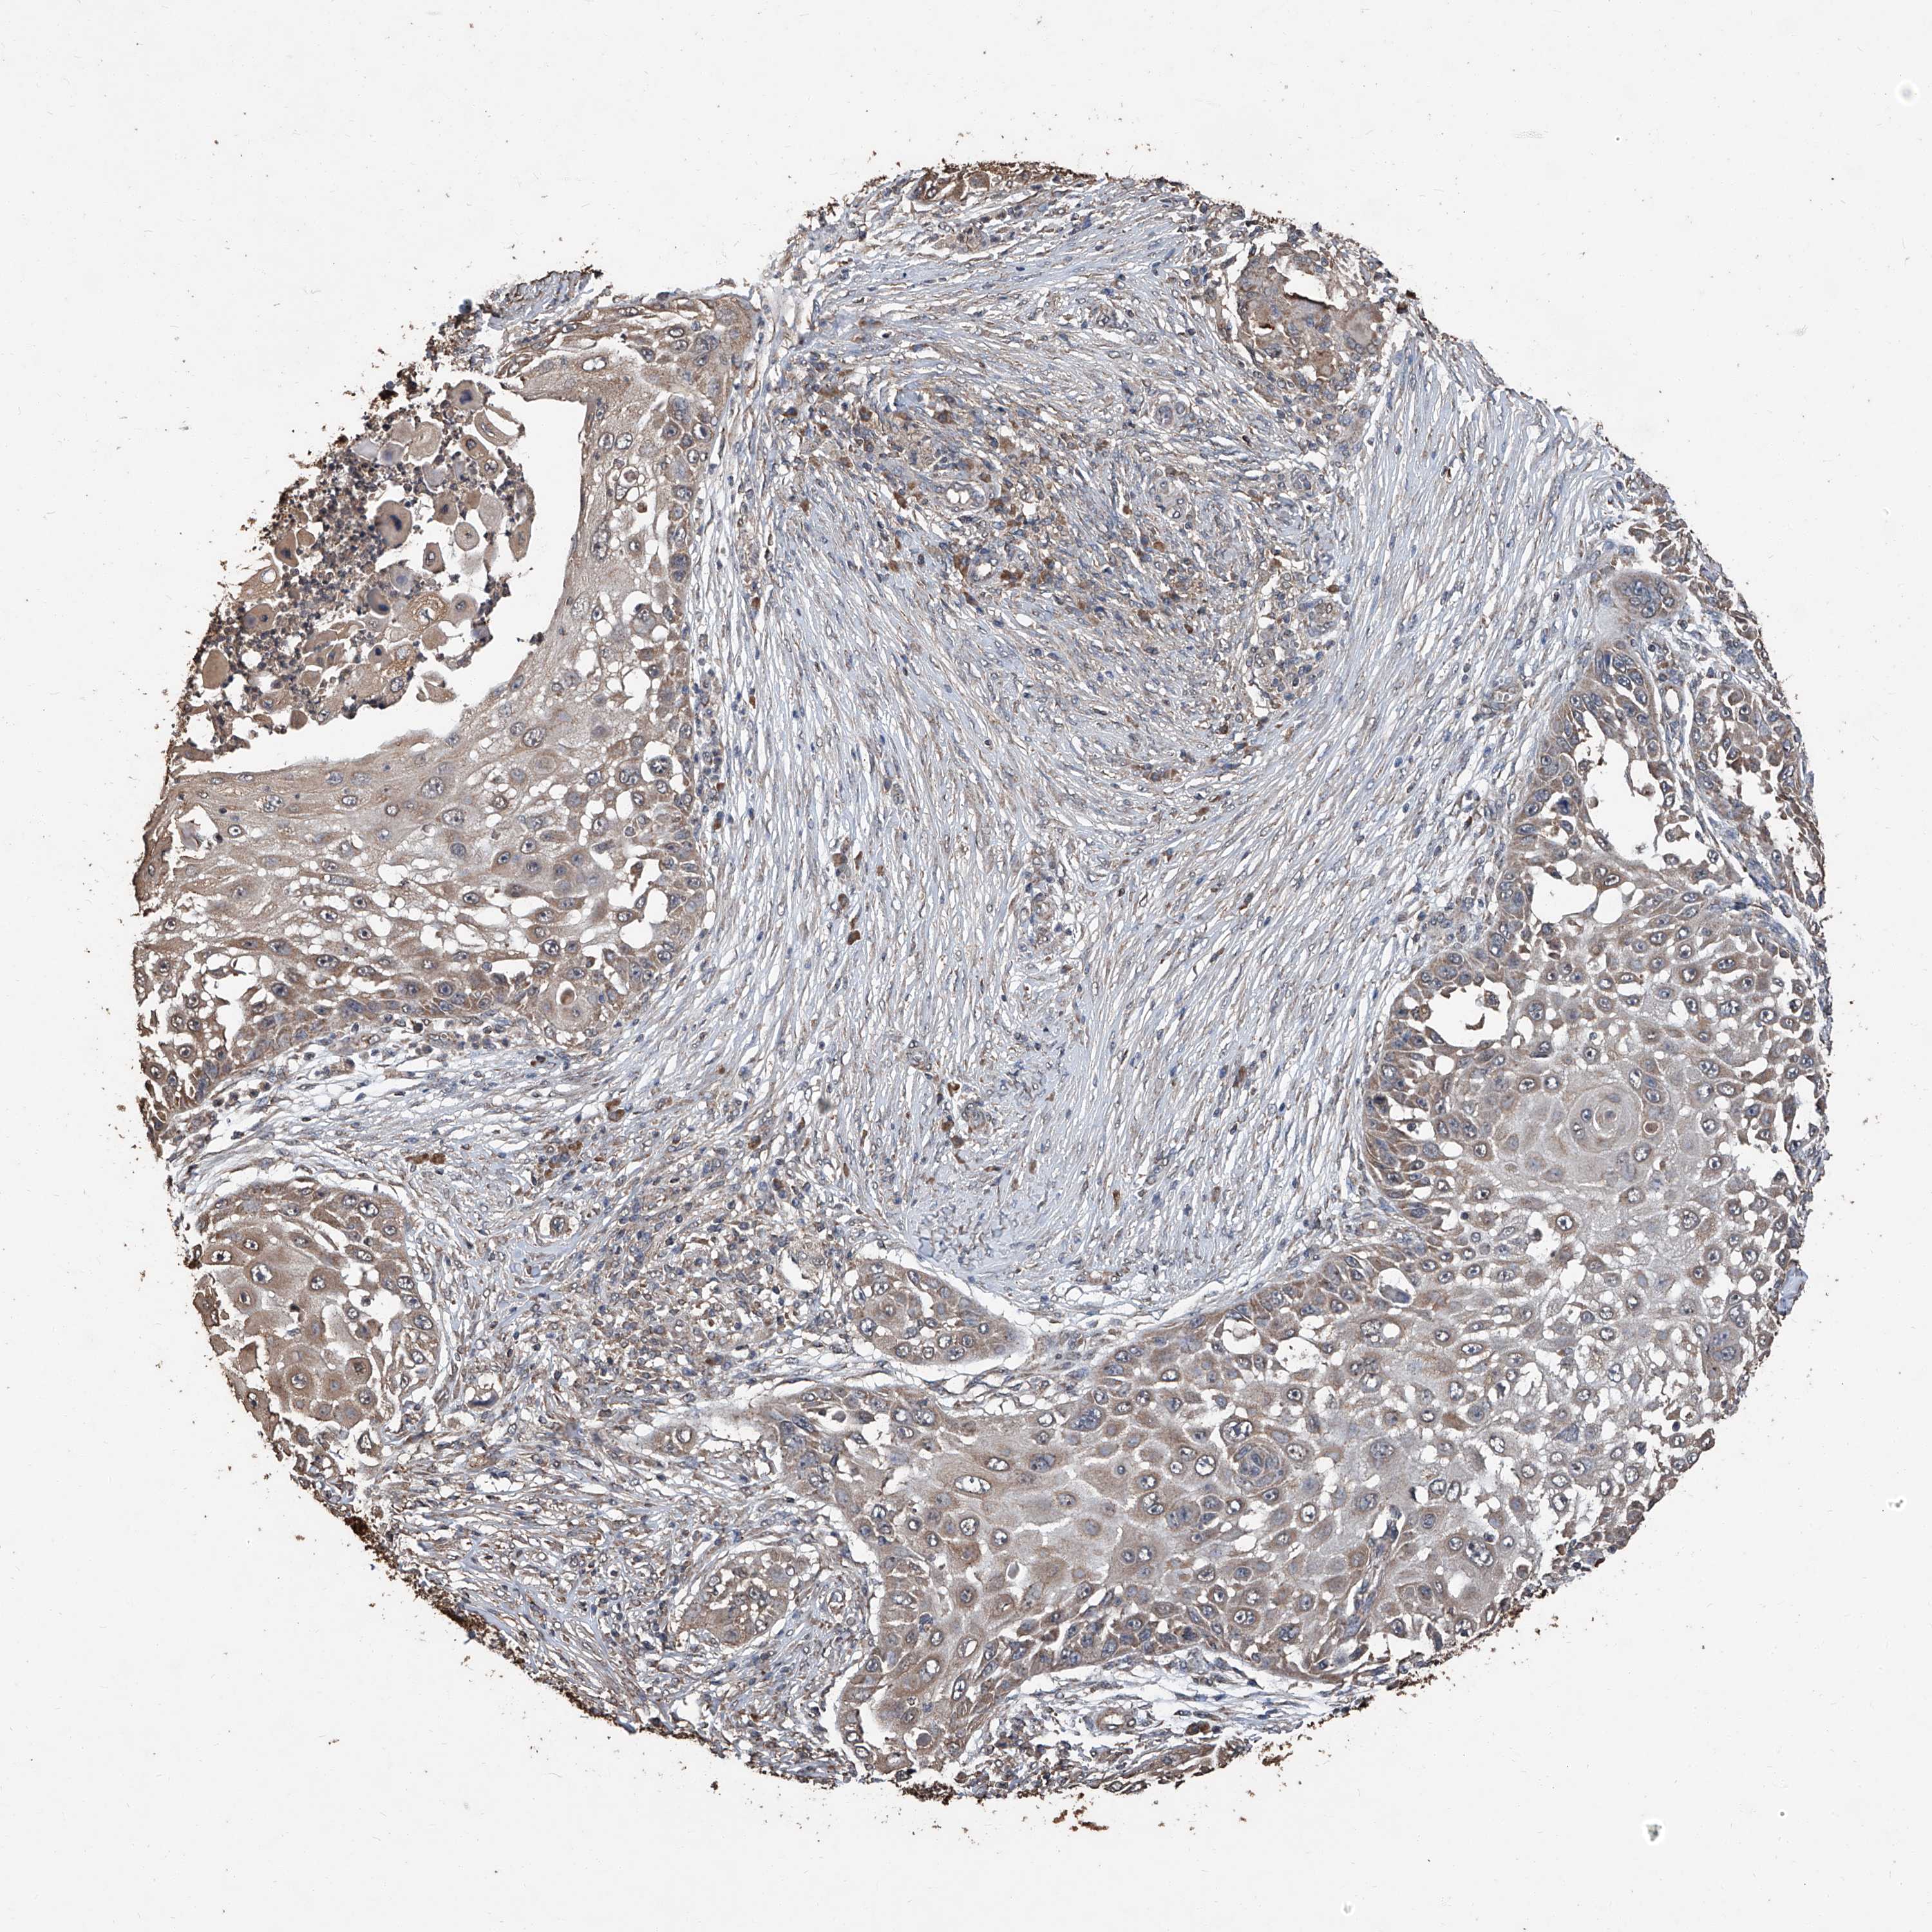

SKIN CANCER - Protein expressioni

A mouse-over function shows sample information and annotation data. Click on an image to view it in a full screen mode. Samples can be filtered based on level of antibody staining by selecting one or several of the following categories: high, medium, low and not detected. The assay and annotation is described here.

Antibody staining in the annotated cell types in the current human tissue is reported as not detected, low, medium, or high, based on conventional immunohistochemistry profiling in selected tissues. This score is based on the combination of the staining intensity and fraction of stained cells.

Each image is clickable and will lead to virtual microscopy that enables deeper exploration of all samples and also displays staining intensity scores, fraction scores and subcellular localization as well as patient and tissue information for each sample.

Antibody HPA064978

Basal cell carcinoma

Squamous cell carcinoma, NOS